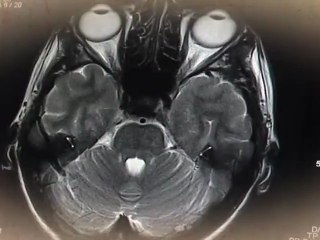

neurones en 3d profondeur de champ mia lens bokeh rendu mental ray br modelisation anim rendu compositing bernard stulzaft